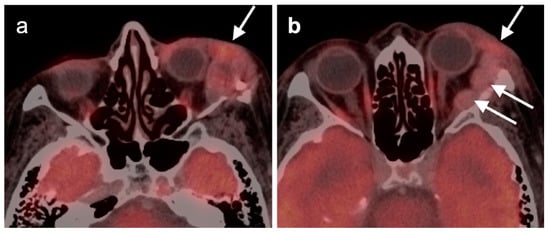

2.4. Sinonasal Tumors

- Eggesbø, H.B. Imaging of sinonasal tumours. Cancer Imaging 2012, 12, 136–152. [Google Scholar] [CrossRef] [PubMed]

- Kawaguchi, M.; Kato, H.; Tomita, H.; Mizuta, K.; Aoki, M.; Hara, A.; Matsuo, M. Imaging Characteristics of Malignant Sinonasal Tumors. J. Clin. Med. 2017, 6, 116. [Google Scholar] [CrossRef] [PubMed]

- Ozturk, K.; Gencturk, M.; Caicedo-Granados, E.; Li, F.; Cayci, Z. Utility of FDG PET/CT in the Characterization of Sinonasal Neoplasms: Analysis of Standardized Uptake Value Parameters. AJR Am. J. Roentgenol. 2018, 211, 1354–1360. [Google Scholar] [CrossRef] [PubMed]